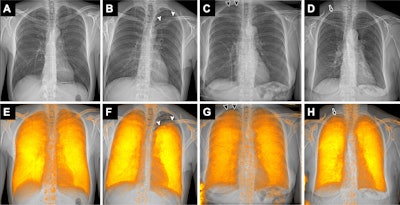

Examples of attenuation-based conventional radiographs (A-D) without and (E-H) with dark-field overlay in a (A, E) 49-year-old male participant without pneumothorax and (B-D, F-G) three participants with pneumothorax. The participants with pneumothorax included (B, F) a 32-year-old male participant with left-sided apical, pronounced pneumothorax (arrowheads), (C, G) a 72-year-old female participant with a small right-sided apical pneumothorax (arrowheads) in whom thoracic drainage has already been inserted on the right side, and (D, H) a 75-year-old female participant with a small right-sided apical pneumothorax (arrow), in whom the pneumothorax is even more obvious on the radiograph with dark-field overlay (arrowheads). (C, G) In the 72-year-old female participant, the pneumothorax line is hard to recognize on the conventional radiograph without overlay (due to overlay of ribs); it appears to be easier to recognize on the image with the dark-field overlay due to the signal loss in that area. (D, H) In the 75-year-old participant, the small pneumothorax is difficult to recognize on both the image without overlay (D) due to ribs in that area, and the image with dark-field overlay (H) due to an ill-defined margin of the dark-field signal combined with residual beam-hardening-induced dark-field signal from the ribs. In G, the dark-field signal in the lower left corner is due to an attached band-aid.Examples of attenuation-based conventional radiographs (A-D) without and (E-H) with dark-field overlay in a (A, E) 49-year-old male participant without pneumothorax and (B-D, F-G) three participants with pneumothorax. The participants with pneumothorax included (B, F) a 32-year-old male participant with left-sided apical, pronounced pneumothorax (arrowheads), (C, G) a 72-year-old female participant with a small right-sided apical pneumothorax (arrowheads) in whom thoracic drainage has already been inserted on the right side, and (D, H) a 75-year-old female participant with a small right-sided apical pneumothorax (arrow), in whom the pneumothorax is even more obvious on the radiograph with dark-field overlay (arrowheads). (C, G) In the 72-year-old female participant, the pneumothorax line is hard to recognize on the conventional radiograph without overlay (due to overlay of ribs); it appears to be easier to recognize on the image with the dark-field overlay due to the signal loss in that area. (D, H) In the 75-year-old participant, the small pneumothorax is difficult to recognize on both the image without overlay (D) due to ribs in that area, and the image with dark-field overlay (H) due to an ill-defined margin of the dark-field signal combined with residual beam-hardening-induced dark-field signal from the ribs. In G, the dark-field signal in the lower left corner is due to an attached band-aid.RSNAKey findings included the following: